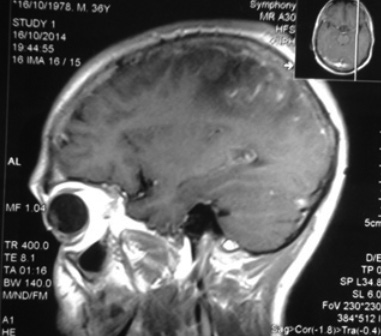

En la figura 7 se tiene un corte sagital por RM con gadolinio, que muestra una lesión córtico-subcortical captadora y difusa, rodeada de edema en el lóbulo parietal izquierdo de un caso de GW comprobado (40).